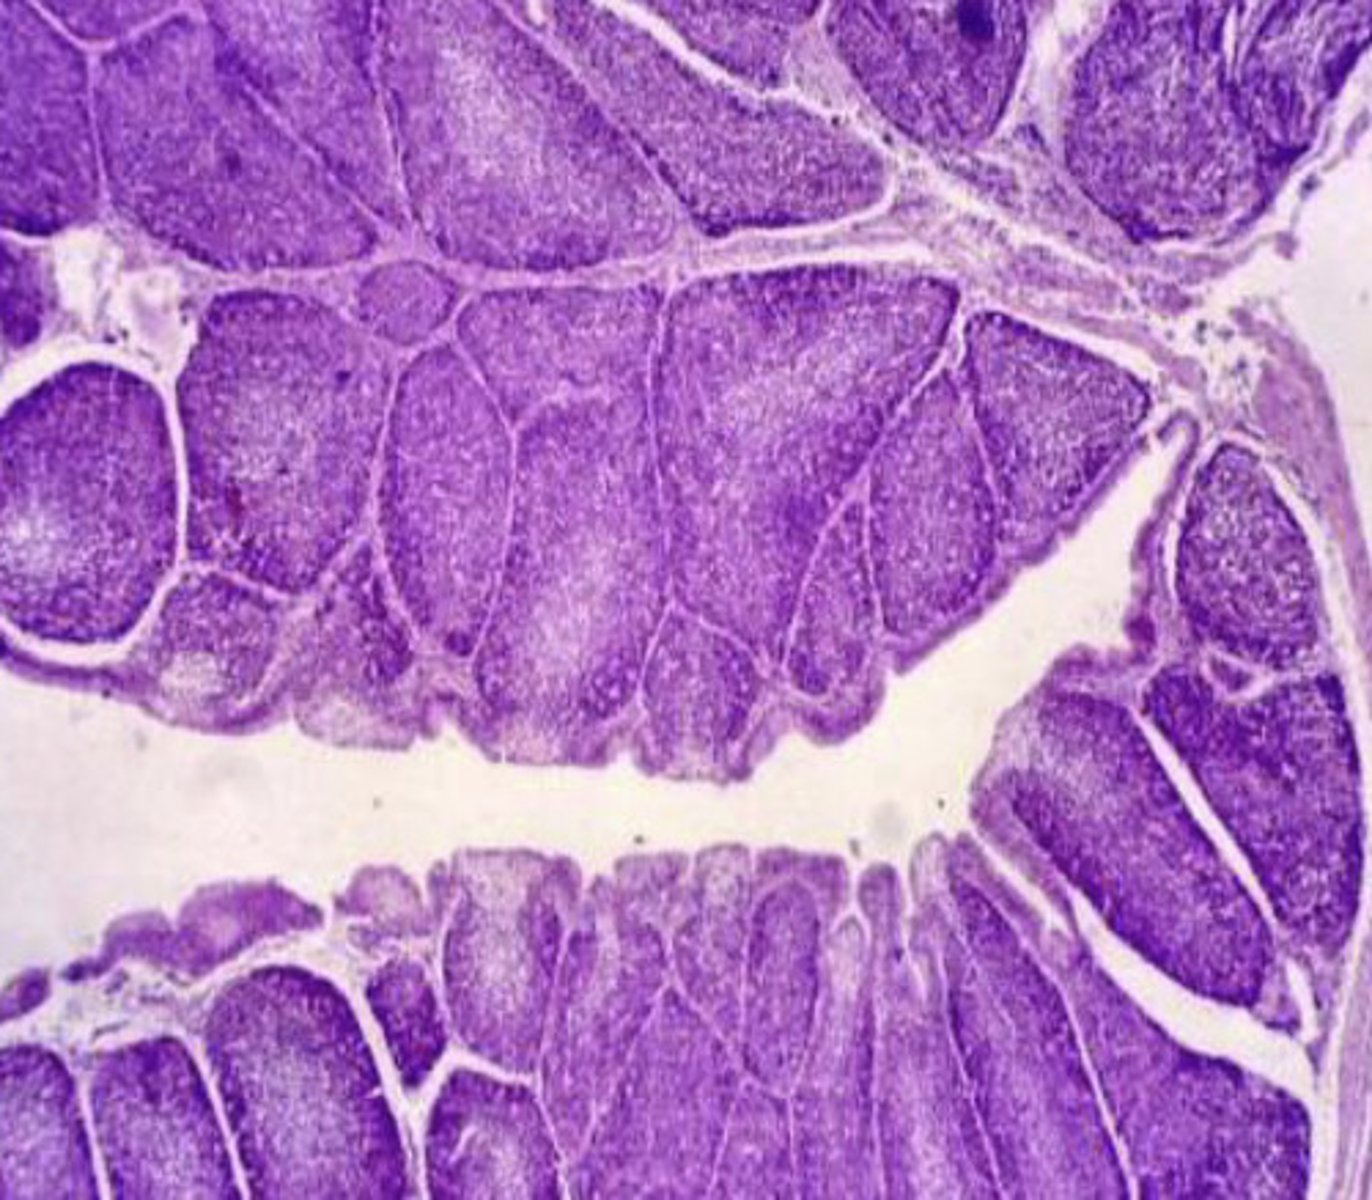

are lymph nodes tubular or parenchymal?

parenchymal-

cortex- follicles with mantle, germinal center, B lymphocytes

medulla- capillaries

what is the structure of lymph nodes?

cortex

what part of the lymph node has follicles with B cells?

interfollicular tissue in the cortex

what part of the lymph node has T cells?

lymph node

what is this?

lymph node

what is this?